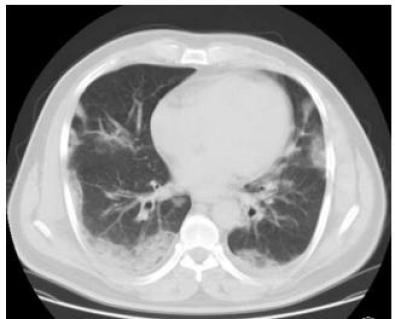

▎间质性肺炎

很多间质性肺炎都会表现为胸膜下为主的病灶,特别是隐源性机化性肺炎,需要结合临床表现具体分析。

下图是嗜酸细胞性肺炎。